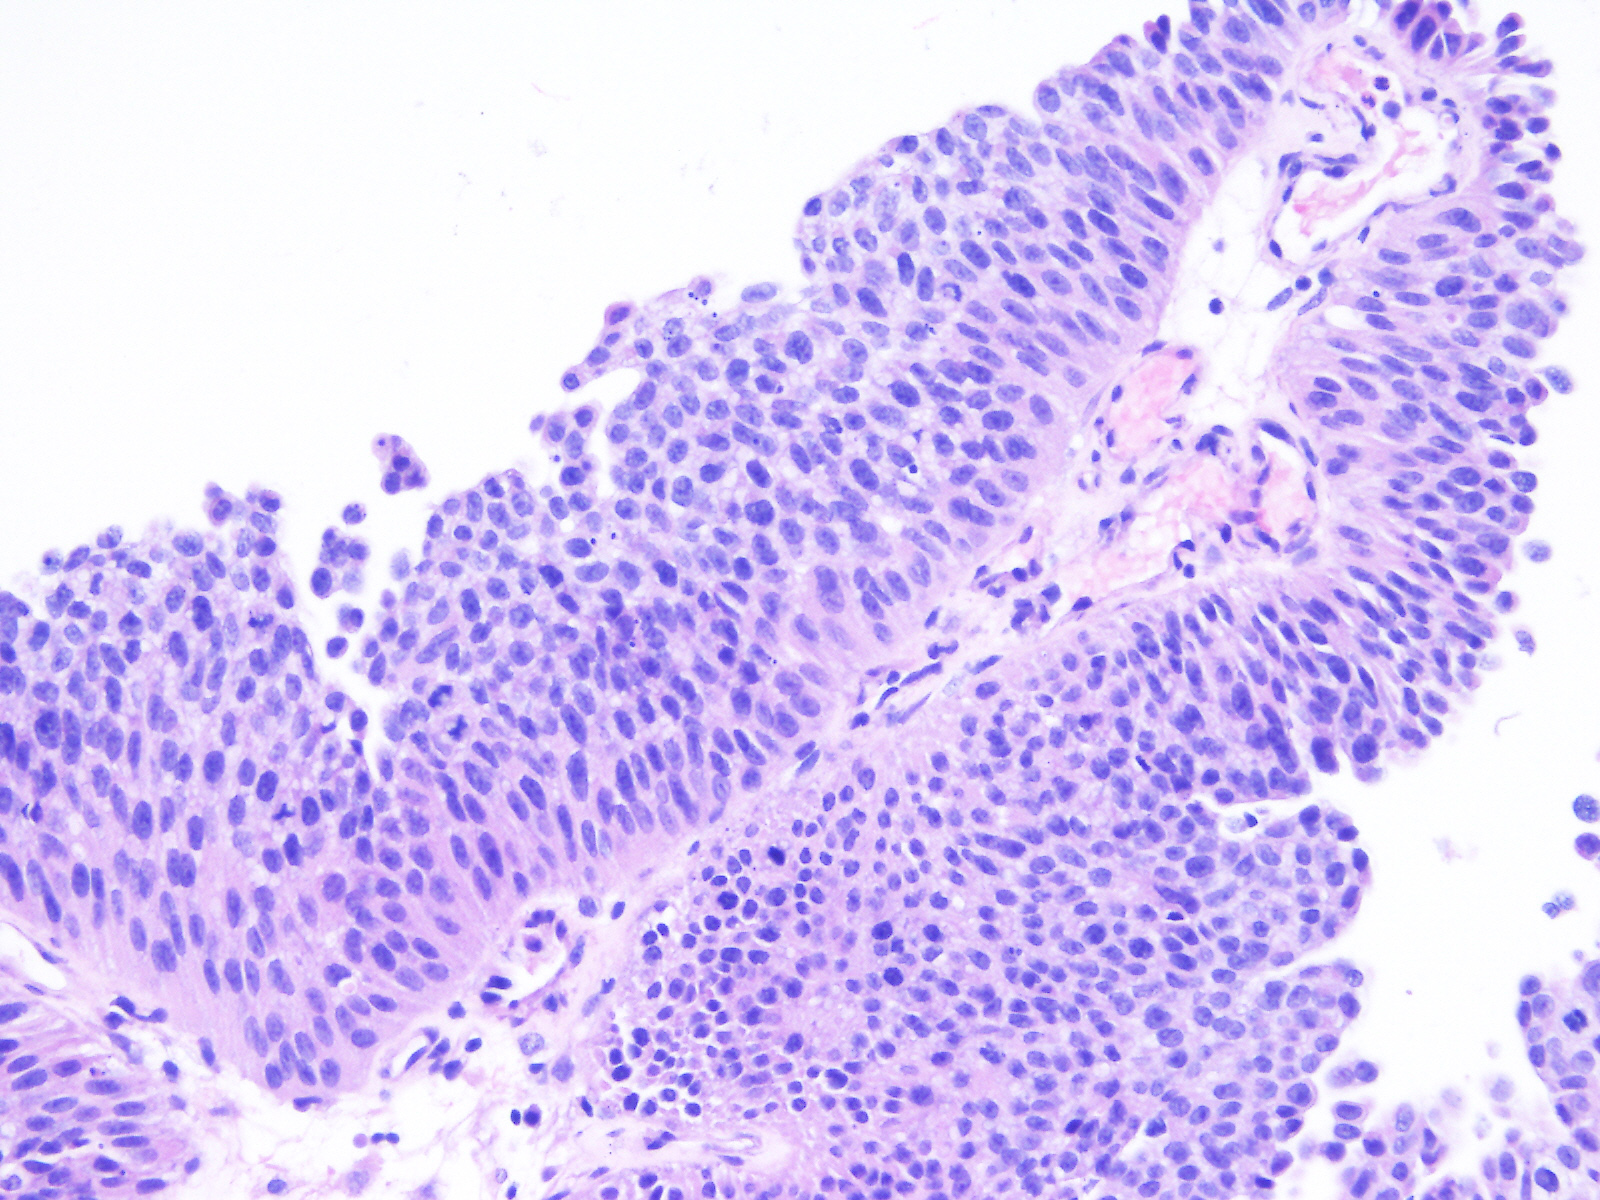

Bladder Papillary Lesions

Case ID: 543